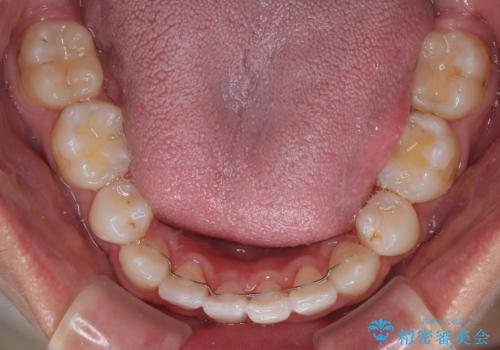

- 今回ご紹介するのは、

「全体的なデコボコ(叢生)」「上下の正中のずれ」 を主訴として来院された20代男性の患者様の症例です。

叢生が強く、歯が並ぶスペースが不足していたため、

上下左右の第一小臼歯を抜歯して、矯正治療のための適切なスペースを確保する計画としました。

上顎左側第一大臼歯に齲蝕が認められたため、矯正治療終了後に 精度の高いセラミックインレー にて修復治療を行いました。